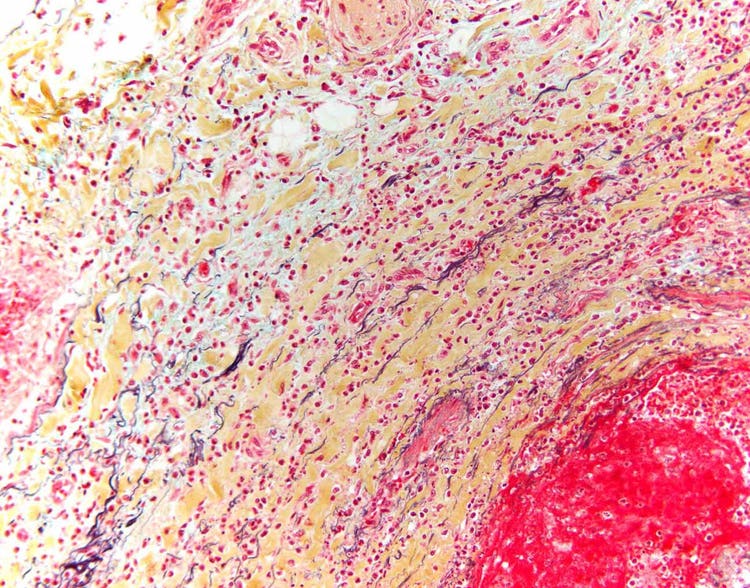

삼색염색법으로 염색된 심장을 현미경으로 관찰한 모습

삼색염색법으로 염색된 손상된 인간 심장의 단면입니다. 파란색 부분은 반흔 조직이고, 빨간색 부분은 생존 세포입니다. DP26 카메라를 사용하여 Olympus BX43 현미경으로 캡처했습니다. 이미지 제공: Marianne Hamel.